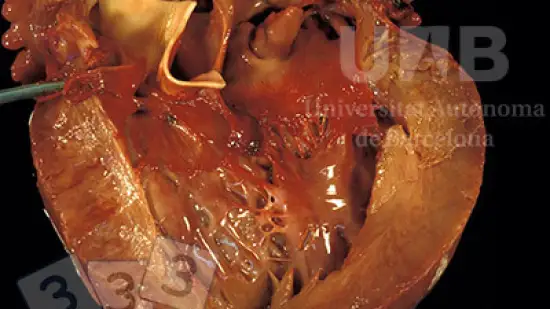

La lésion observée sur ce cœur correspond à...